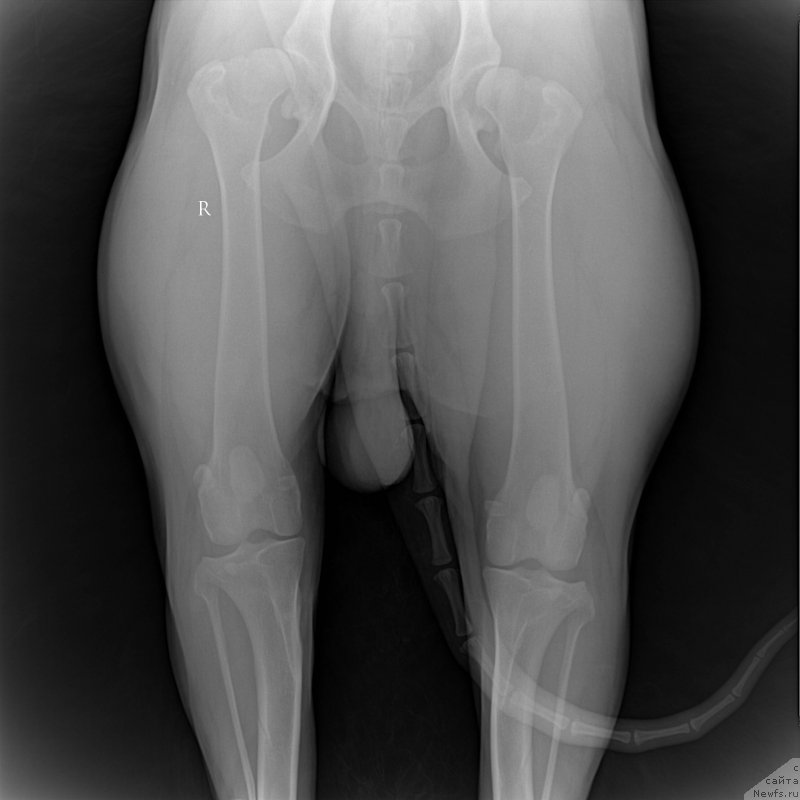

Подскажите,

какова степень дисплазии на этом снимке?

Он захромал, стали сразу ставить диагноз дисплазия , большие степени.И вот решили сделать ренген...

По снимку рентгена у меня возникли какие-то смутные вопросы-что-то вот как-то не поняла.Думала, либо мне кажется, либо что-то как-то не так.